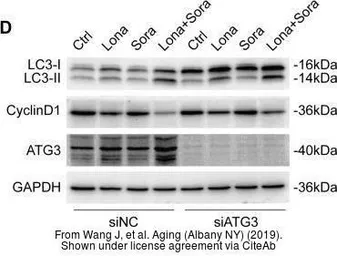

The data was published in the Cancer Med in 2020. PMID: 32324343